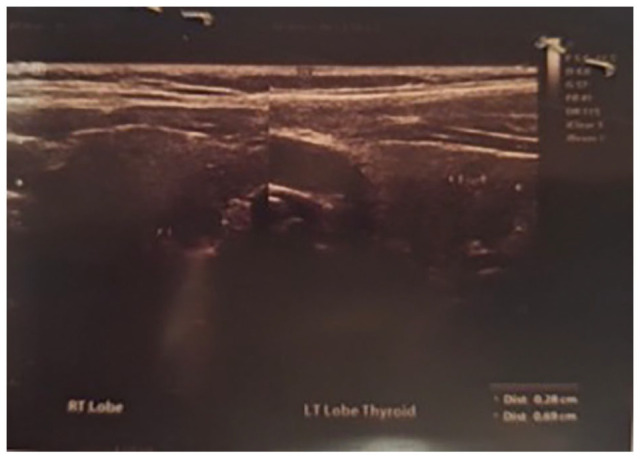

COVID-19 是由严重急性呼吸系统综合征冠状病毒 2(SARS-CoV-2)引起的一种全球性传染病,它不仅最初指急性表现,而且还包括被称为长 COVID-19 的慢性症状。长COVID-19给全球医疗系统带来了沉重负担。该综合征包括一系列持续性健康问题,持续时间长短不一,对患者日常生活的影响也不尽相同。长 COVID-19 综合征的一个显著特点是新发自身免疫性疾病的出现,这些疾病可能会在免疫反应发生改变的易感患者中引发。COVID 后患者常见的自身免疫性疾病包括自身免疫性溶血性贫血、免疫性血小板减少性紫癜、自身免疫性甲状腺疾病、川崎病、格林-巴利综合征等,但相关疾病发生的证据并不明确。我们报告了一例女性类风湿性关节炎患者在感染 SARS-CoV-2 后出现自身免疫性甲状腺疾病、成人潜伏性自身免疫性糖尿病(LADA)和恶性贫血的病例。

COVID-19, a global epidemic of infectious disease caused by Severe Acute Respiratory Syndrome Coronavirus 2 (SARS-CoV-2), not only initially refers to acute manifestations but also chronic symptoms known as Long COVID-19. Long COVID-19 represents a significant burden to healthcare systems worldwide. This syndrome encompasses a wide range of continuing health problems with variable durations and consequences for patients' everyday lives. A notable aspect of Long COVID-19 is the emergence of new-onset autoimmune diseases that could be triggered in predisposed patients with altered immune responses. Common autoimmune conditions that arise in post-COVID patients include autoimmune hemolytic anemia, immune thrombocytopenic purpura, autoimmune thyroid diseases, Kawasaki disease, Guillain-Barre syndrome, etc., but with unclear evidence of associated disease occurrence. We present a case of a female rheumatoid arthritis patient who developed autoimmune thyroid disease, latent autoimmune diabetes of adults (LADA), and pernicious anemia after SARS-CoV-2 infection.